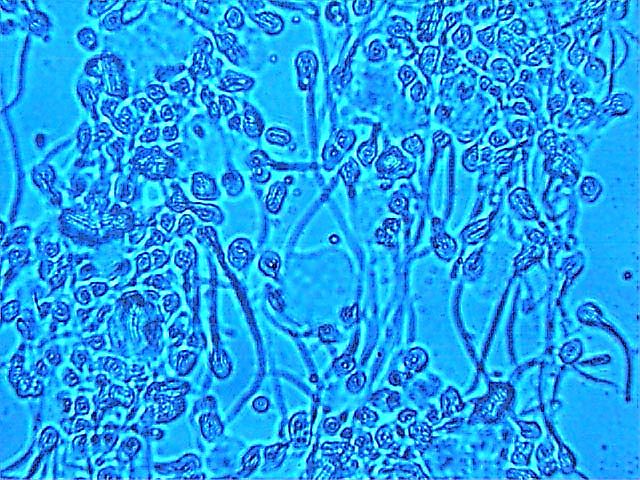

примеры изображений

Модель АФС-500-2 содержит встроенный микроскоп, что позволяет визуально контролировать состояние и подвижность клеток в измерительной кювете в реальном времени на экране монитора компьютера.